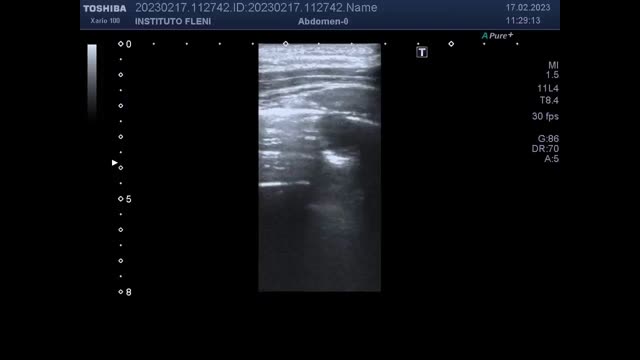

A-33-year-old man, with family history of Rendu–Osler–Weber syndrome, presented with seizures. Brain tomography showed a parietal brain lesion, and chest tomography reported a hyperdense nodular image in the right middle lobe. Lung point of care ultrasound (POCUS) was performed, and a round hypoechoic image with anterograde and retrograde flows was shown (Fig. 1), which moved with the ventilatory pattern. CT pulmonary scan revealed a dilated vascular structure in a coiled arrangement in the right middle lobe with multiple pulmonary arterial branches directly communicating with the pulmonary veins, compatible with complex pulmonary arteriovenous malformation (PAVM). Brain biopsy revealed a brain abscess, so antibiotics were started. Later, he was referred for angioembolisation.

Lung CT revealed a dilated vascular structure in the right middle lobe close to the pleura (A and B, white arrow), compatible with PAVM. Pulmonary echography showed a right parasternal hypoechoic image with an intraluminal hyperechoic area, compatible with thrombosis (C, white arrow). Doppler mode revealed a ‘mosaic-pattern’ indicative of mixing of arterial and venous blood consistent with PAVMs (D). Here, the anterograde and retrograde flow form a “ying-yang sign” (asterisk). Pulsed doppler image demonstrated arterial and venous flows (E).

PAVMs are rare, abnormal low resistance vascular structures that connect a pulmonary artery to a pulmonary vein, resulting in an intrapulmonary right-to-left shunt. The preferred screening test for PAVM is transthoracic contrast echocardiography, while thin section CT scanning is the imaging of choice to diagnose a PAVM.1 However, under certain circumstances, lung POCUS can demonstrate PAVMs. Pulmonary ultrasound perform with a good acoustic window can detect vascular malformations close to pleura, or only partially embedding the parenchyma.2 POCUS is a useful tool to rule out differential diagnosis of pulmonary images.